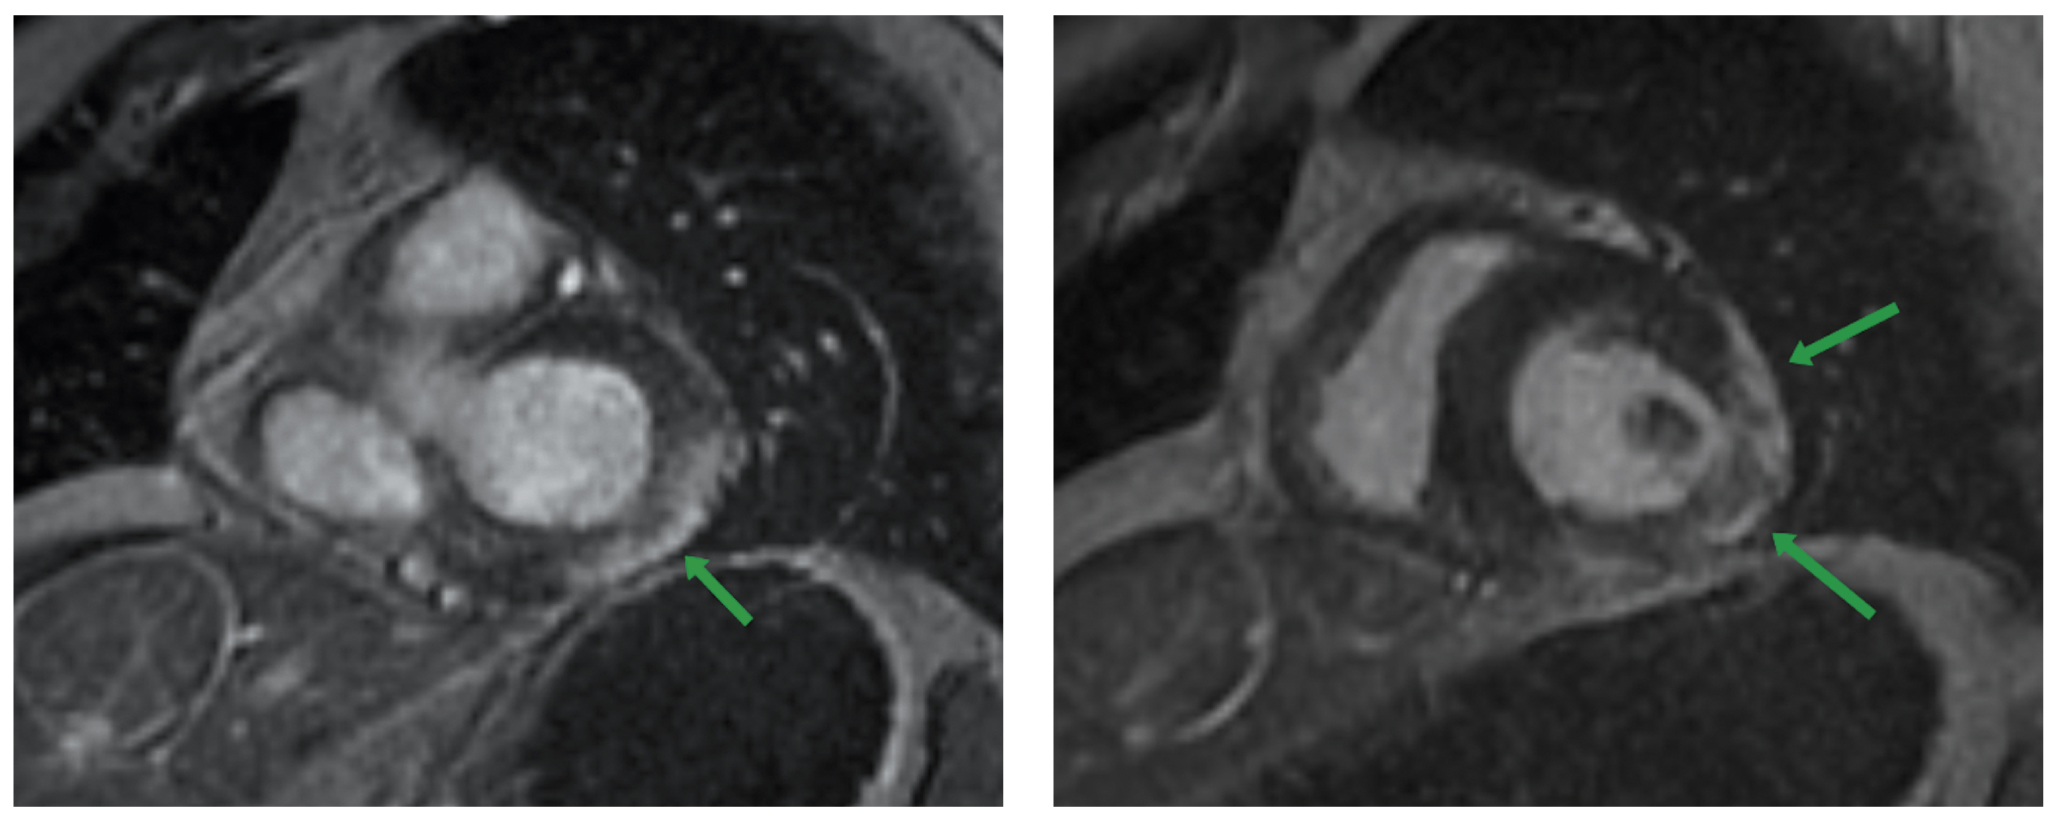

При воспалении сердечной мышцы повышается проницаемость клеточных мембран, в результате чего происходит увеличение количества жидкости в миокарде. На МР-томограммах этот процесс отображается в виде участков отёка и повышения сигнала на Т2 и STIR. Отёк миокарда может быть диффузным или очаговым (рис. 1) [11]. Необходимо учитывать, что отёчные изменения могут сочетаться с участками некроза, а при отсутствии фиброза являются обратимыми [12, 13].

Рис. 1. Магнитно-резонансная томография сердца, последовательность STIR, изображения по короткой оси сердца: а — локальный участок отёка миокарда межжелудочковой перегородки (стрелка); б — диффузная зона отёка миокарда передней и боковой стенки левого желудочка (стрелка).

Fig. 1. Cardiac magnetic resonance imaging, STIR sequence, short axis plane: а — the arrow indicates the local area of myocardial edema of the interventricular septum; б — the arrow indicates а the diffuse zone of myocardial edema of the anterior and lateral walls of the left ventricle.